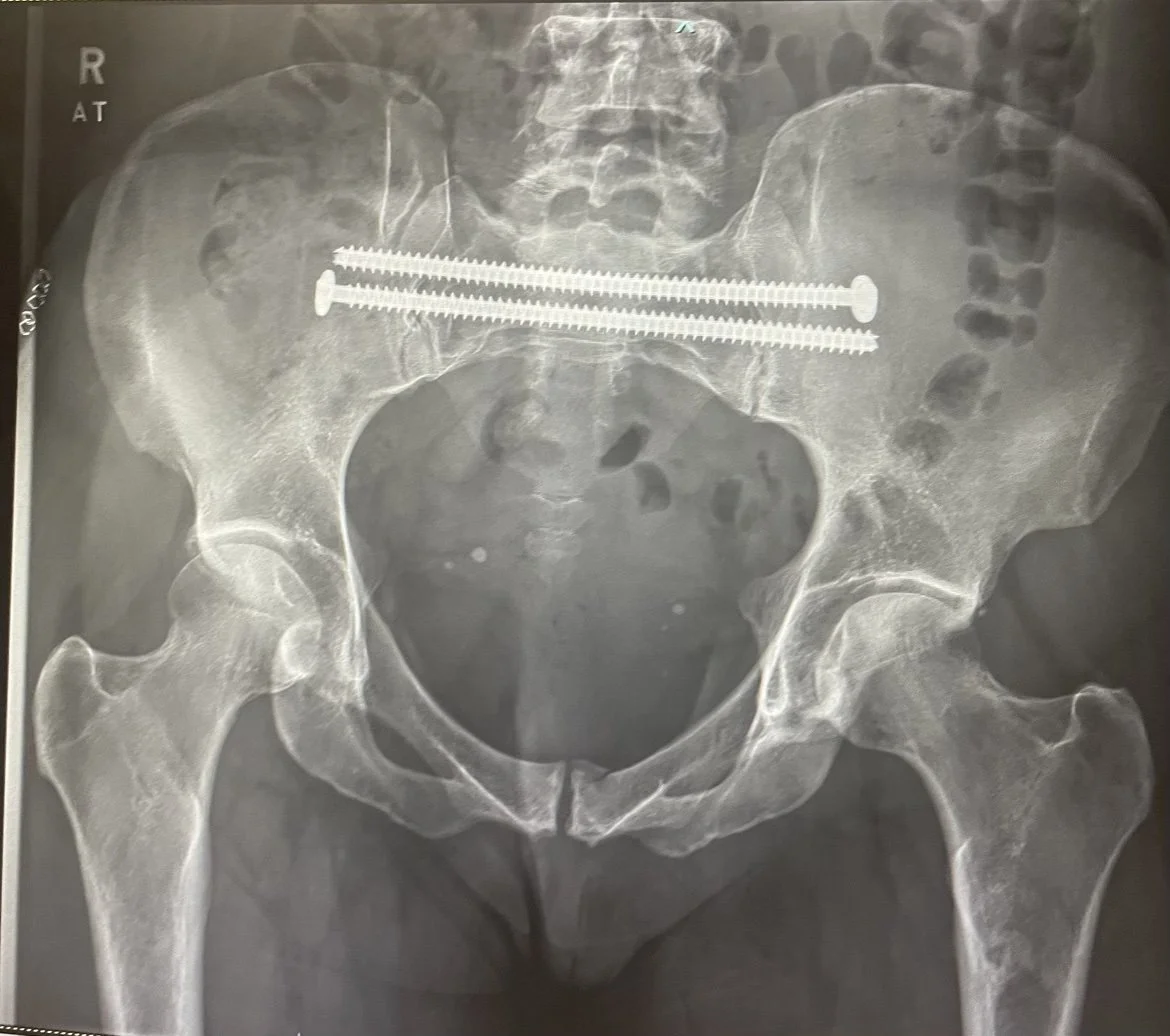

• Broek sustained the following injuries:

• Closed fracture of both acetabula

So she had two surgeries: one for clavicle one for pelvis.